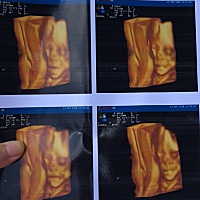

历经千辛万苦……愿宝宝健康快乐的成长!